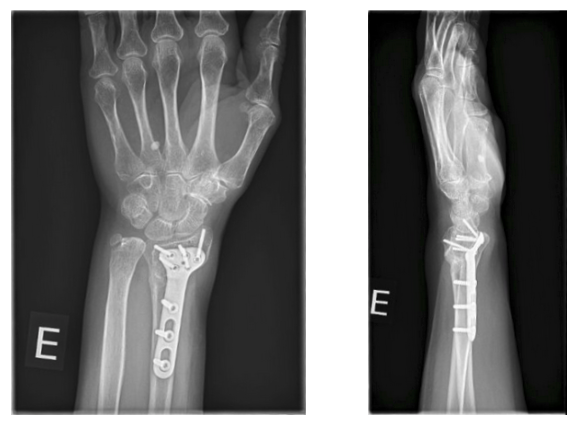

Final follow-up: May 17, 2023

• Full pronation-supination preserved

• Flexion 55° / Extension 65°

• No pain

6-month follow-up